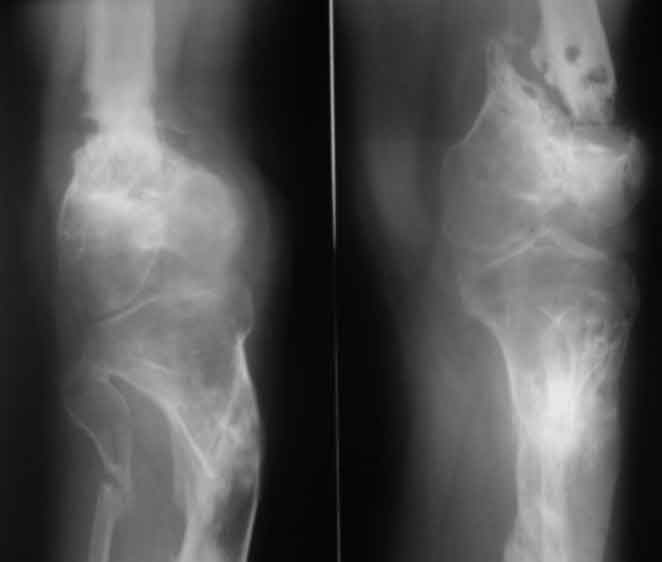

Псевдоартроз дистального отдела бедра. Distal femur nonunion

Псевдоартроз дистального отдела бедра. Distal femur nonunion у пациента 26 лет

Открытый перелом н/3 бедра и в/3 голени в 2006 году. выполнен малоинвазивный накостный остеосинтез после заживления ран (снимки утеряны), через 3 мес после остеосинтеза - глубокое нагноение, консультировался и лечился с 2006 года в одном из лучших НИИ. многократные остеотомии, компрессии, дистракции. В августе 2010 - снят аппарат в поликлинике в центре, рекомендации - ходить в ортезе, показаться через 2 мес, консультирован в другом НИИ - рекомендовано дообследование (приличный список, каждый раз добавлено нечто новое).

В итоге попал к нам, движения в к/с отсутствуют, подвижность только на уровне ложняка, передненаружная поверхность области к/с представляет собой многочисленные рубцы от доступов, закрытых свищевых ходов. Свищей нет на протяжении 3 лет, кровь не воспалительная, СРБ - отс.

Коленный сустав не работает и вряд ли заработает, ось голени нарушена, дистальный фрагмент бедра очень короткий. Если думать о восстановлении опороспособности ноги, то, мне кажется, только совместив интрамедуллярный остеосинтез длинным гвоздем трансартикулярно с артродезом коленного сустава и коррегирующей остеотомией большеберцовой (и малой берцовой) кости.